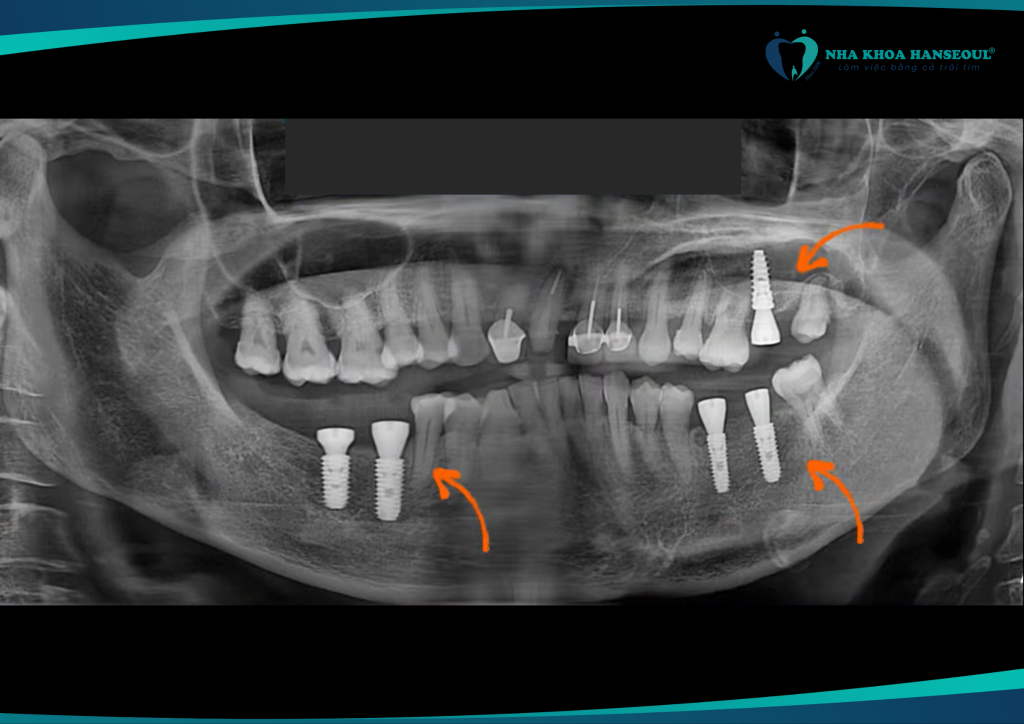

Sau khi được bác sĩ chuyên môn thăm khám và tư vấn, cô Thơm được chỉ định cấy ghép răng Implant với công nghệ Hansafe. Đây là công nghệ định vị trụ tiên tiến được ứng dụng độc quyền tại Hanseoul.

Công nghệ Hansafe tại Hanseoul không chỉ giúp đảm bảo độ chính xác khi cấy trụ mà còn rút ngắn thời gian phục hồi, phù hợp cho người lớn tuổi hoặc Việt kiều ít có thời gian tái khám thường xuyên.

- Đặt trụ chuẩn xác tới từng milimet

- Hạn chế xâm lấn – giảm đau, ít sưng

- Rút ngắn thời gian điều trị

- An toàn cao – đặc biệt cho người có bệnh lý nền